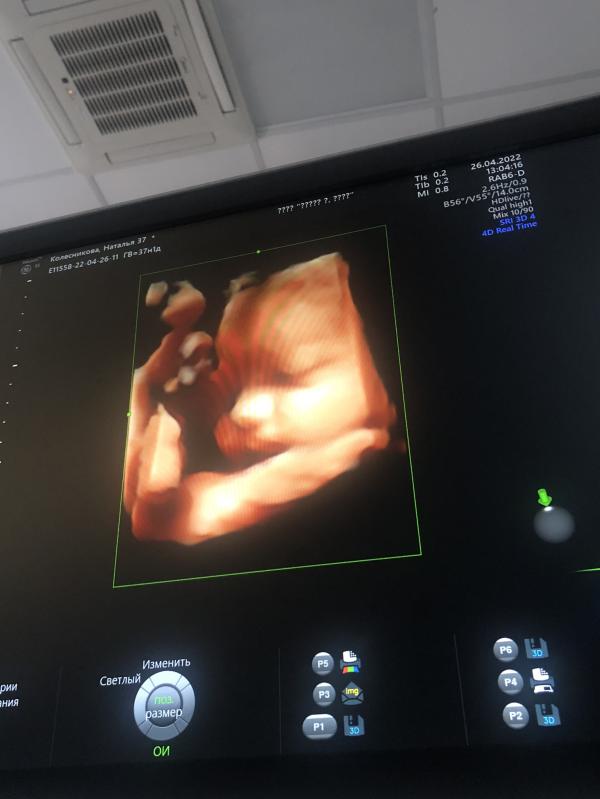

Оставлю здесь на память 😊 сегодня я решилась таки узнать кто же у меня будет … пам -пам … мальчик 3500 вес на сроке 37,1 нед . Девочки , подскажите пожалуйста как назвать … даже не думала над именем 🙄 , а теперь голову ломаю … ничего интересного придумать не могу